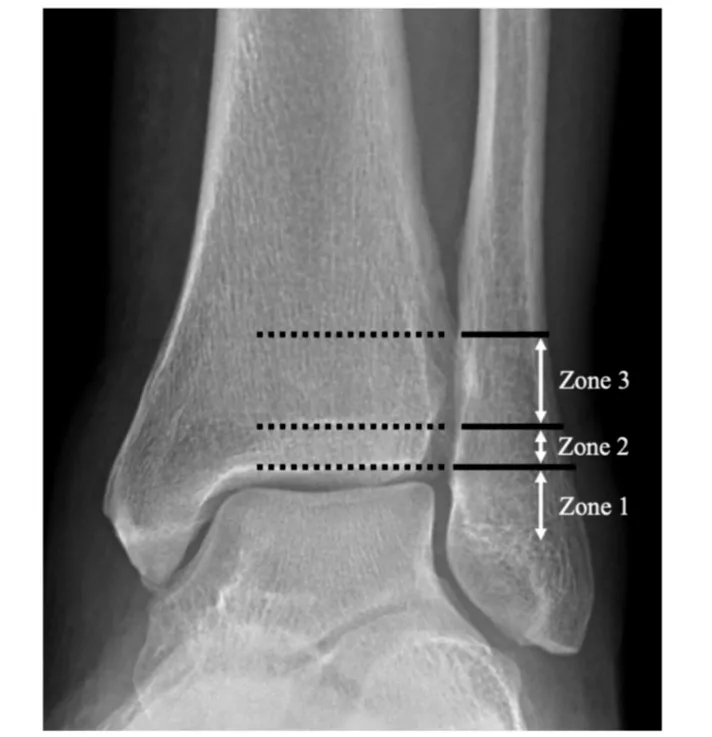

Lauge-Hansen分型与Danis-Webe分型为最常见的踝关节骨折分型,在对下胫腓韧带损伤的指导意义上,旋后外旋II°骨折通常认为合并下胫腓前韧带的损伤,下胫腓联合趋于稳定,可能无需下胫腓联合螺钉固定。而Danis-Weber B型骨折定义为骨折位于下胫腓联合水平,可能合并下胫腓联合损伤。